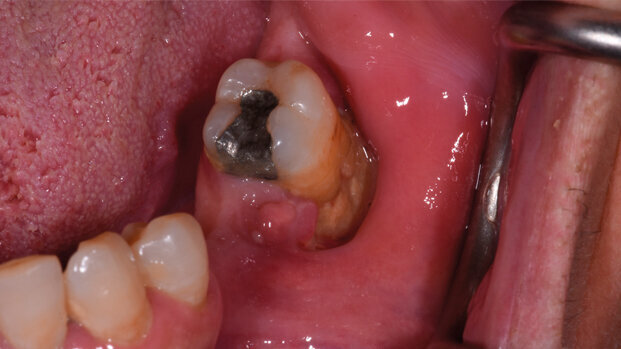

Tra i farmaci anti-riassorbitivi, i BP sono ancora i più utilizzati in formulazioni invasive (e.v.) e per dosi cumulative/tempi elevati (con conseguente maggiore concentrazione nel compartimento osseo), esponendo tali soggetti a un maggiore rischio d’insorgenza di ONJ anche per l’azione sinergica di altri fattori di rischio fortemente associati alla patologia. Tra i fattori di rischio sistemici annoveriamo i trattamenti con farmaci chemioterapici e/o steroidei e la presenza di co-morbidità favorenti (ad esempio, diabete, anemia, immunosoppressione)11-13. Mentre tra i fattori di rischio locali troviamo: la presenza di patologia infiammatoria dento-parodontale, le procedure chirurgiche dento-alveolare e l’utilizzo di dispositivi protesici incongrui (ad attività lesiva nei confronti della barriera meccanica mucosale)12,14.

In particolare, l’odontoiatra ha progressivamente assunto negli anni un ruolo fondamentale non solo nella diagnosi precoce di ONJ, attraverso l’intercettazione dei segni clinico-radiologici precoci della malattia, ma soprattutto nella sua prevenzione. È ampiamente documentato come l’incidenza di ONJ sia fortemente correlata a fattori di rischio locali.

Tali condizioni, influiscono sul profilo di rischio del paziente oncologico e devono, pertanto, essere opportunamente gestite dallo specialista della salute orale.